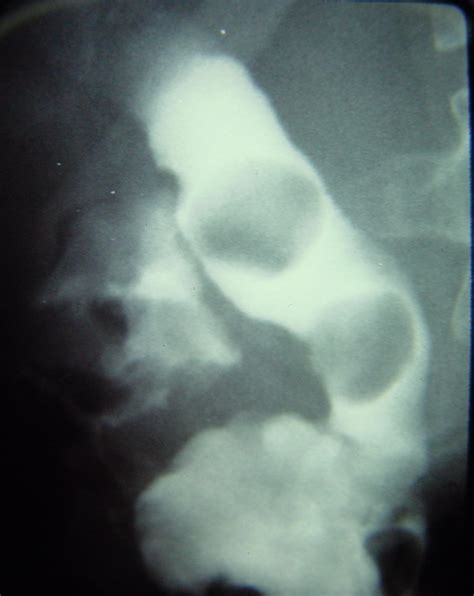

Comparing Diagnostic Methods

Diagnosing bile duct stones requires a combination of clinical history and advanced imaging. Doctors use several diagnostic tools to locate the obstruction and determine the best course of action. Below is a comparison of the most common diagnostic procedures:

ERCP Direct visualization and removal of stones. Minimally Invasive